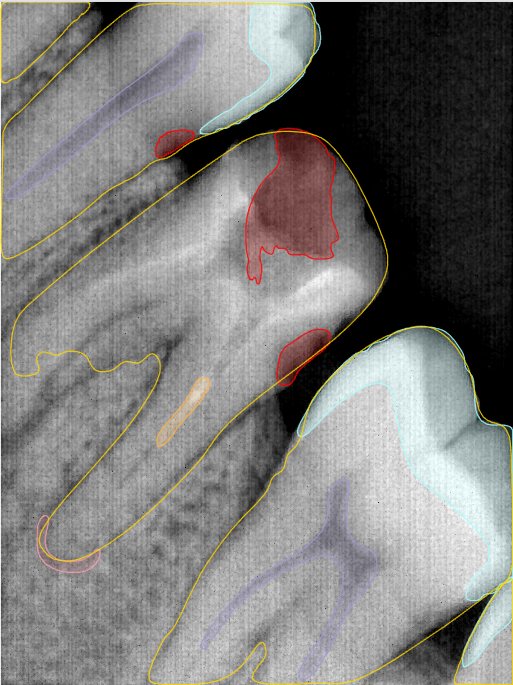

第二版算法问题测试

| 第一版 | 第二版 | 是否解决 | |

|---|---|---|---|

![]() | ![]() ![]() 边角识别有问题 龋齿识别不全 牙髓识别不全 | ![]() | 解决 |

![]() | ![]() 边角识别有问题 识别信息有误 自查(牙冠识别不全) | ![]() | 解决 |

![]() | ![]() ![]() 边角识别有误 大范围填充识别遗漏 | ![]() | 解决 |

![]() | ![]() 识别信息不全 | ![]() | 解决 |

![]() | ![]() ![]() 边角问题 牙胶识别不全 牙冠识别不全 | ![]() | 解决 |

![]() 换图片 | ![]() | ![]() 牙冠部分稍微白了一些就识别成小范围修补,部分判断异常 | 部分解决,修复类略敏感,牙冠部分稍微白了一些就识别成小范围修补,部分判断异常。 |

![]() | ![]() ![]() 牙冠识别不全 牙髓不全 根尖炎龋齿识别有误 | ![]() | 解决 |

![]() | ![]() | ![]() | 解决 |

![]() 换图片 | ![]() | ![]() | 解决 |

![]() | ![]() 牙冠识别有误 | ![]() | 解决 |

![]() 换图片 | ![]() ![]() 边角识别有误 | ![]() 修复类敏感 | 部分解决,图像过白,导致修复类判断异常。 |

![]() 换图片 | ![]() 牙冠识别不全 | ![]() 修复类敏感 | 部分解决,图像过白,导致修复类判断异常 |

结论:修复类出现了不鲁棒的情况,后续需要加入轮廓的扩充数据进行增强。